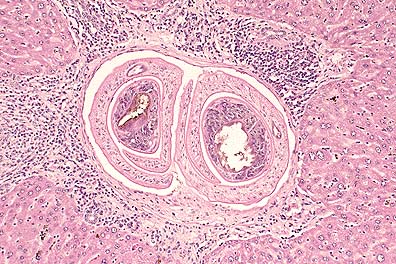

Adult S. mansoni in the hepatic portal vasculature of an experimentally inoculated mouse. (HE, 200X, 57K)

Granulomatous inflammation characteized by foreign body giant macrophages surrounding an egg of S. manson in an experimentally inoculated mouse. (HE, 400X, 46K)

Contributor's Diagnosis and Comments: Liver: hepatitis, chronic, portal and bridging, multifocal, moderate, with granuloma formation, trematode eggs, pigment, and intravascular trematode parasites - etiology consistent with Schistosoma mansoni.

Schistosomes are digenetic trematodes that live within the blood vessels of their hosts. Their distribution is determined by the distribution of their intermediate hosts (a nonoperculated snail in the case of S. mansoni). Schistosome eggs hatch in the water releasing a ciliated miracidium which penetrates the snail. Cercariae develop in the snail and are released in the water where they are ingested or penetrate the skin to infect the host. Metacercaria migrate to the liver, pair within the portal circulation, reach maturity, and deposit eggs which penetrate capillary walls and leave the body via the feces or the urine to continue the life cycle.

Schistosomiasis is one of the most common causes of human morbidity and mortality. The adult parasites live in the host's veins and can incorporate host antigens, avoiding an immune response. The eggs that remain in tissues cause inflammation that progresses from neutrophils and eosinophils to granulomas with multinucleate giant cells. Urinary schistosomiasis has been associated with carcinomas of the urinary bladder in man and nonhuman primates.

AFIP Diagnosis: Liver: Hepatitis, portal and bridging, chronic, multifocal, moderate, with granulomas, trematode eggs, and intravascular trematodes, Swiss-Webster mouse, rodent, etiology consistent with Schistosoma mansoni.

Conference Note: Schistosomiasis is a snail-borne fluke infection prevalent in domestic animals, nonhuman primates, and humans in Asia, Africa, and other tropical and subtropical areas. Species that parasitize mammals include those of the genera Schistosoma, Hetrobilharzia and Orientobilharzia. The only schistosome of importance in the United States is Heterobilharzia americana, which has been reported in raccoons, bobcats and dogs in the southern United States. Schistosomes are different from other flukes in that they live in blood vessels, have separate sexes, have nonoperculated eggs with a spine, and do not have an encysted metacercaria stage.

Adult schistosomes, while alive in the veins, generally provoke little or no host response because they incorporate host antigens (primarily blood group antigens) into the outer membranous tegument and are therefore recognized as "self." Phlebitis with intimal proliferation and occasionally thrombosis may result from the presence of adult flukes. Vascular lesions are more severe when the adult worms die or are trapped at unusual sites. Eggs that escape into the tissues stimulate considerable inflammation. Penetration of the skin by cercariae results in urticaria, itching and formation of tiny nodules which elevate the epidermis. In humans, this often is caused by avian schistosomes and is commonly called "swimmer's itch."

The diagnosis of schistosomiasis can be readily made on histopathologic sections with the finding of intravascular trematodes and/or the characteristic spiny, non-operculated eggs.